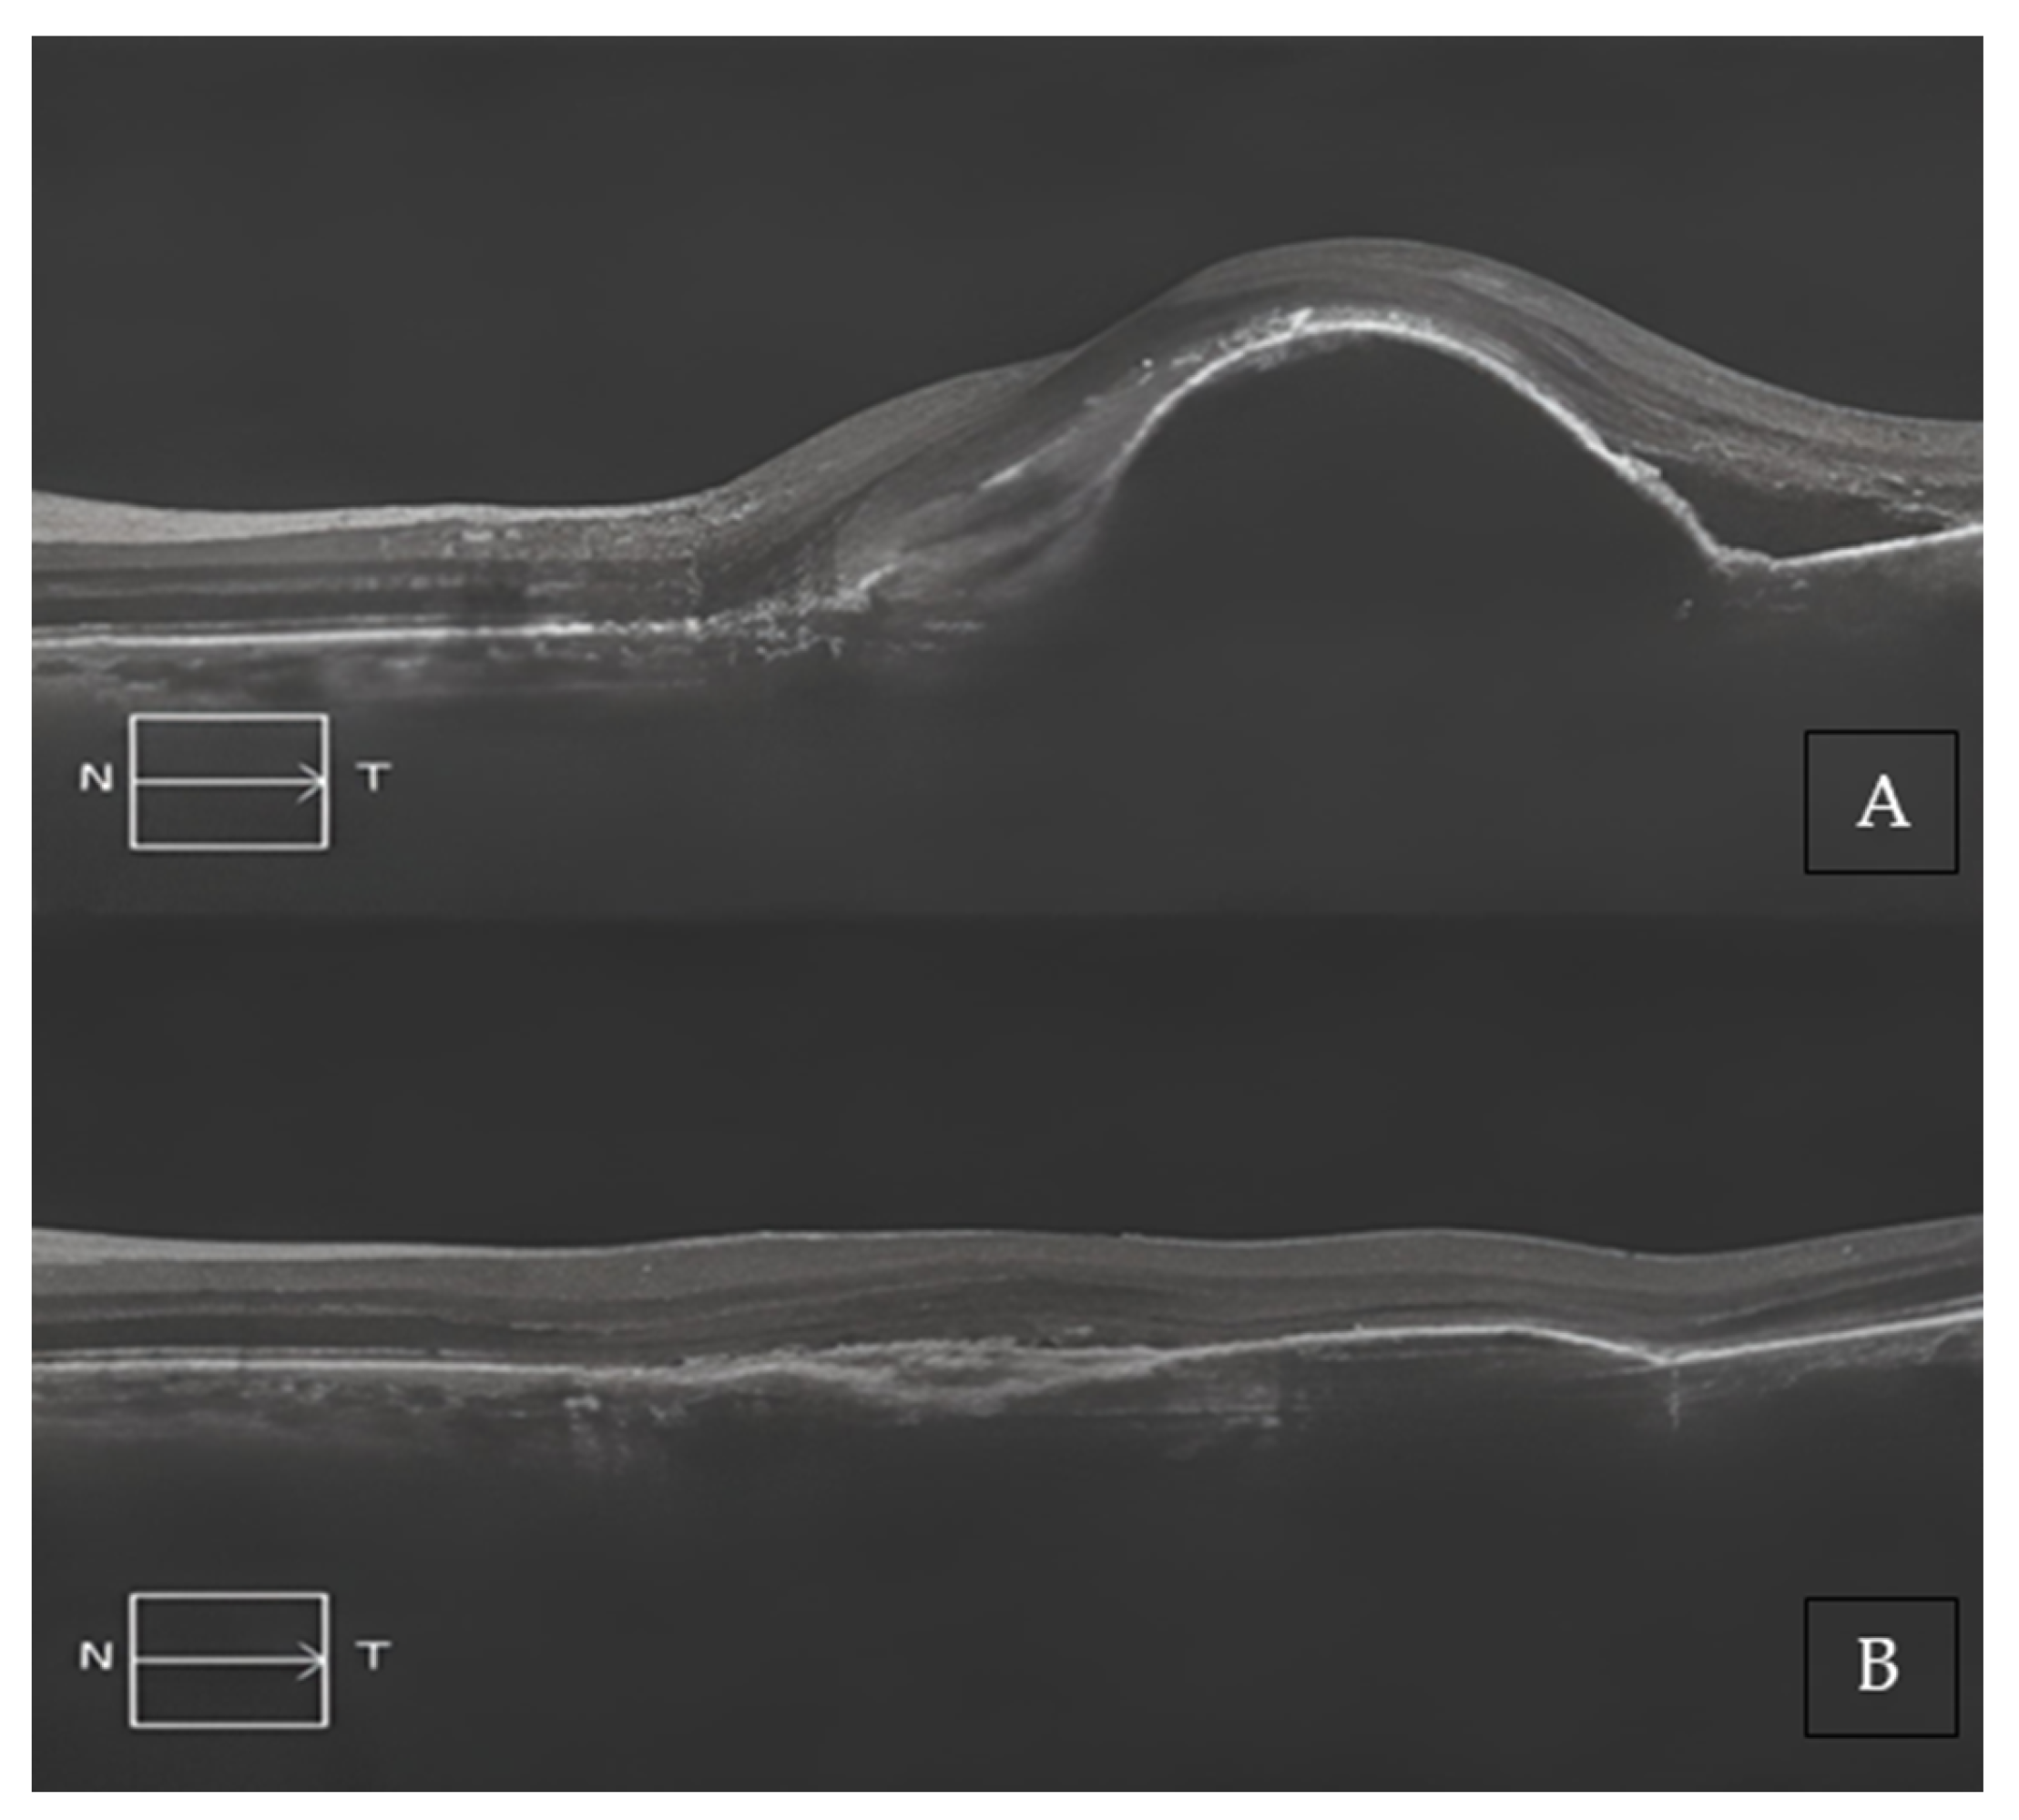

Two representative cases of patients from our cohort, before and after treatment with Brolucizumab, are shown in Figure 2A,B and Figure 3A,B.

Figure 3. (A) Baseline SD-OCT scan acquired with Maestro 3D OCT-1 (Topcon Corporation, Tokyo, Japan) of a treatment-naïve patient displaying a large, pigmented epithelium detachment (PED), and subretinal edema. (B) A 4-month SD-OCT scan acquired with Maestro 3D OCT-1 (Topcon Corporation, Tokyo, Japan) displayed a complete reabsorption of the PED and a modest residual sub-RPE hyper-reflective band.